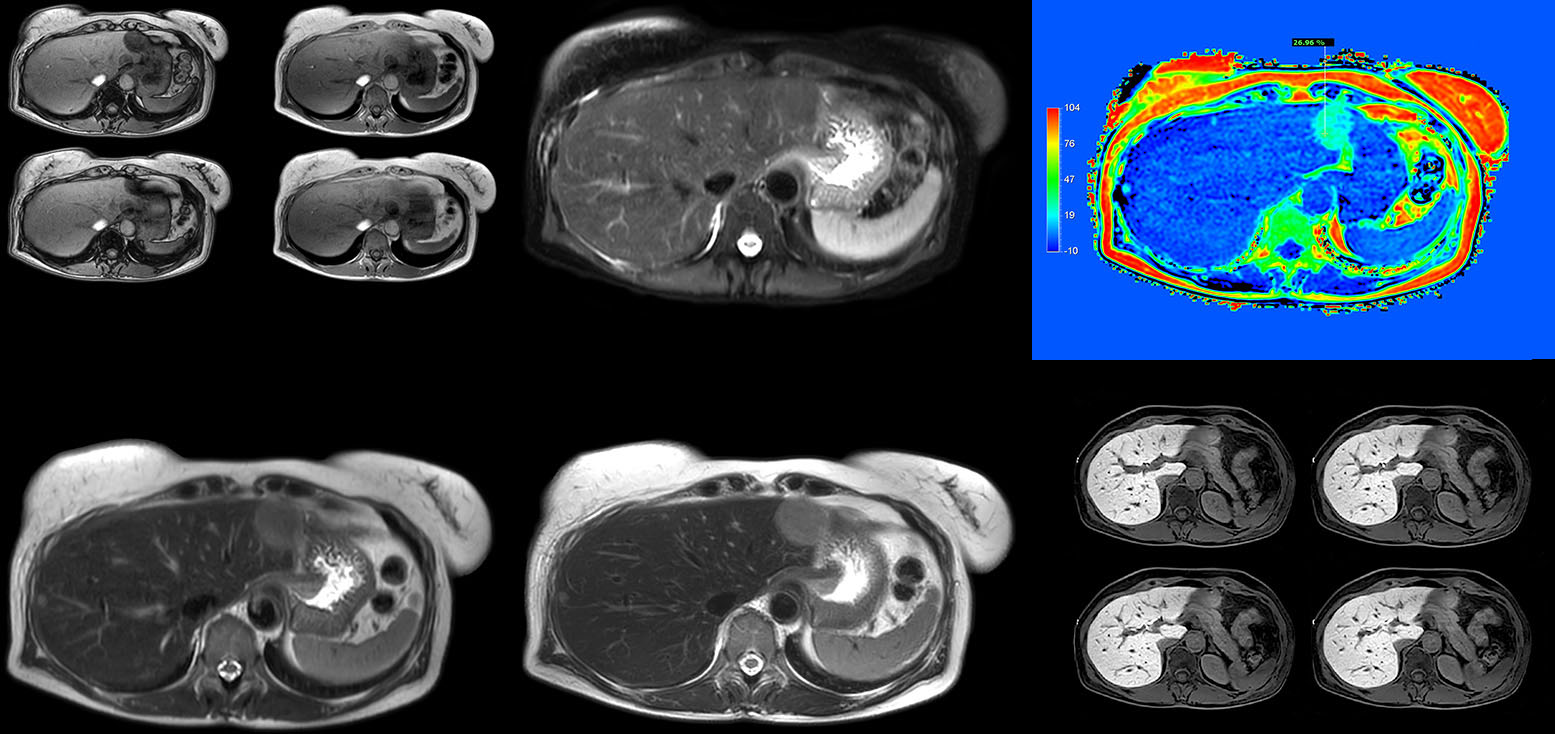

“Using MultiVane XD motion correction, we are now able to acquire high spatial resolution T2-weighted images without seeing relevant motion,” says Dr. Kukuk. “It’s a great technique to obtain high spatial resolution images of the pancreas or the liver, as well as the surrounding organs and tissues. MultiVane XD can be combined with dS SENSE parallel imaging, allowing us to reduce specific absorption rates (SAR), acquire high spatial resolution in short acquisition times, and at the same time reduce artifacts caused by motion in adjacent tissues and organs.”

“In comparison to single shot T2-weighted TSE, this approach with MultiVane XD motion suppression provides higher spatial resolution. In addition, it is especially valuable in patients who cannot hold their breath or have some disabilities. My impression is that this sequence has the potential to substitute for, or even replace, the T2-weighted single shot sequence in our liver exams, because of good and consistent delineation of small lesions.”

“We have performed a study comparing mDIXON Quant fat percentages with results from histopathology. The correlation with different histologic methods was very good and also the correlation with MR spectroscopy was far above 0.9 – a nearly perfect correlation,” says Dr. Kukuk.

“So, this fast mDIXON Quant sequence allows us to diagnose, quantify, and follow up – that’s the real advantage. Our gastroenterologists were easily convinced, as they are well aware of the limitations of ultrasound and the risks of liver biopsy.”

“Fatty liver disease is a common condition. Studies found a prevalence of non-alcoholic fatty liver disease in up to 44% in the general European population [1]. Liver fat cannot be quantified by ultrasound or CT, so biopsy has been the way to quantify fatty liver disease so far,” says Dr. Kukuk. “mDIXON Quant now allows non-invasive quantification of liver fat, which is valuable for both diagnosis and follow-up during dietary changes or therapy, for instance in hepatitis C.”

“The mDIXON Quant fat fraction maps provide quantitative information and also anatomical detail. The sequence is fast, usually taking about 16 seconds, which is just a breath hold for most patients. It definitely improves our efficiency.”